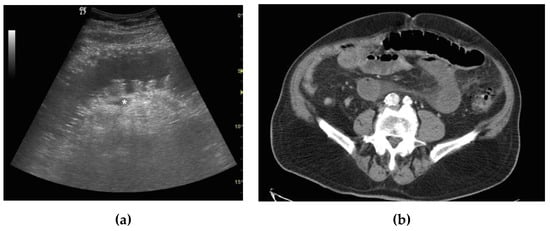

| Bowel loops diameter | Increased | Increased | Increased |

| Parietal thickness | Normal | Normal or increased | Increased |

| Valvulae conniventes | Not thickened | Not thickened | Thickened |

| Peristalsis | Present and/or hyperkinetic | Decreased | Absent |

| Free fluid | Absent | Present | Present |